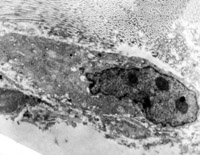

5-2-8 伤后第10天,皮肤附件上皮细胞成簇分布,核仁边集,内质网扩张,胞质内含较多张力原纤维 TEM×6000